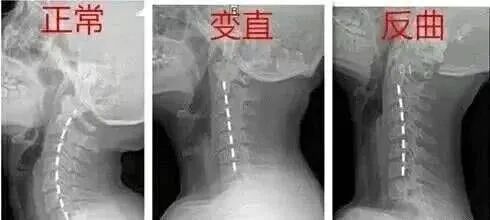

大家都知道,颈椎的正常生理曲度是前凸的,而胸椎是后凸的。在颈胸交界刚好是前凸后凸的交界,当颈椎下段过度前凸而胸椎上段过度后凸时就形成了骨性的颈胸交界骨性突起。